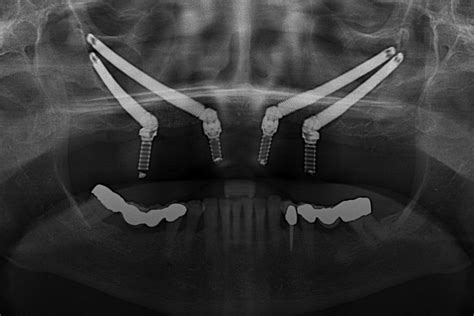

Lo que distingue al doctor González Valenzuela es su afán por la innovación y su preocupación por ser pionero en tratamientos relacionados con el campo de la implantología. En este sentido, el doctor fue pionero en Zaragoza en la utilización de implantes cigomáticos. Se trata de unos implantes que se colocan en el pómulo en casos donde el paciente padece una falta extrema de hueso. La intervención precisa de anestesia general y el paciente tendrá que pasar la noche hospitalizado.

Con 40 años de experiencia profesional, el doctor González Valenzuela domina la odontología y la cirugía maxilofacial en el campo la implantología. Cuenta con una amplia experiencia en colocación de implantes de carga inmediata.

Desde hace más de quince años, la Clínica Dental Dr. González Valenzuela realiza la técnica de cirugía guiada por ordenador, que consiste en la colocación del implante en el sitio más preciso con la ayuda de una férula quirúrgica, lo que permite conseguir una estética excelente. La intervención se planifica previamente con un programa informático y scanner.

El procedimiento tiene una serie de ventajas sobre la cirugía tradicional, como una mayor precisión; minimiza la incisión, evitando tener que descubrir el hueso para colocar el implante; un tiempo más reducido de la intervención y un postoperatorio significativamente más llevadero. “Al no tener que abrir la encía, se acorta mucho el tiempo quirúrgico y se disminuye el dolor postoperatorio”, señala el especialista.